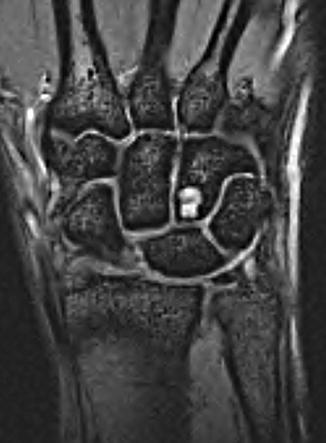

20+ Avascular Necrosis Of Carpal Bones UK. Avascular necrosis of the carpal bones. The sensitivity of this imaging modality allows differentiation of subtle changes in the bone marrow signal.

Carpal bone fractures can be difficult to detect on conventional xray and may require ct for diagnosis. These are located in the wrist area. Avascular necrosis, death of bone tissue caused by a lack of blood supply to the affected area.

Avascular necrosis (avn), also called osteonecrosis or bone infarction, is death of bone tissue due to interruption of the blood supply. Early on, there may be no symptoms. Avascular necrosis (avn) is a bone disease that occurs by temporary or permanent loss of blood supply to one or more bones. It most commonly happens in the.